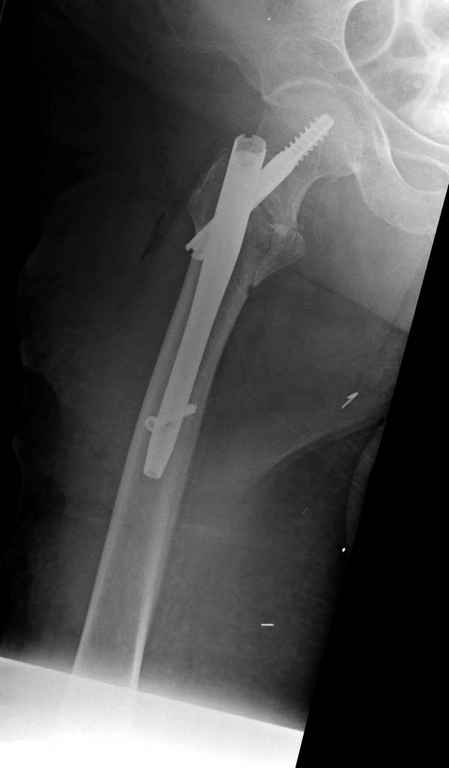

Вашему вниманию представляется похожий случай, пациентке 70, осложнился в течение одного месяца после операции. Ревизия с заменой сустава, кабельная фиксация на трохантер. При установке в дистальном диафизе обнаружен тонкий кортикальный слой и сделана профилактика от возможного перелома аллографтом.